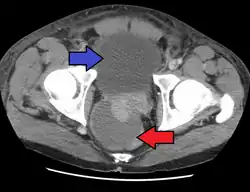

Abscess of the prostate (red arrow) resulting in urinary retention (blue arrow)